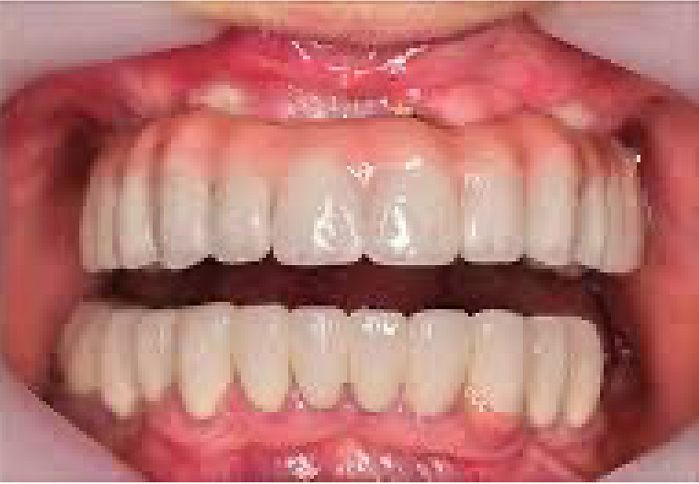

三週完成 全口植牙造齒

全口固定植牙假牙

數位化牙科:透過科技+牙科技術的結合,運用口掃機、電腦2D或者3D的數位軟體影像製作,搭配電腦斷層影像,將病患的資料上傳至雲端。讓醫師、牙技師、患者能夠同步溝通,降低治療期待值的誤差,同時,減少不必要的失誤與縮短治療時間。 - 6. 牙冠增長術 2025.09.02